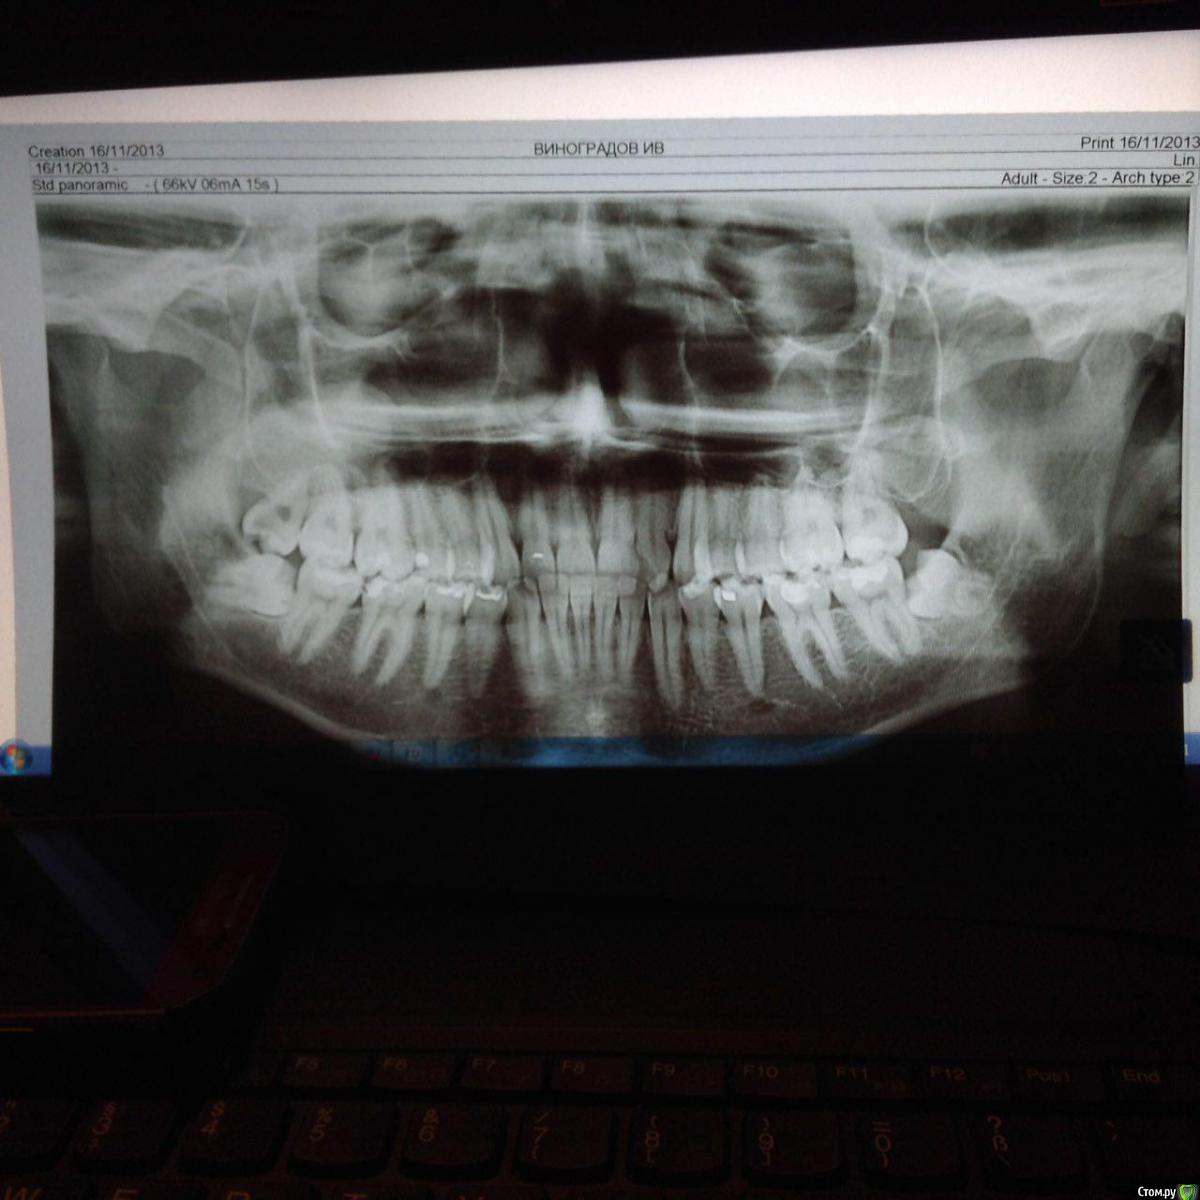

Света88888 Опубликовано 12 августа, 2015 Поделиться Опубликовано 12 августа, 2015 Добрый день, уважаемые Гуру! Пожалуйста, подтвердите, или опровергните, заключение, что все 3 зуба мудрости являются ретинированными.Очень интересует ваше мнение насчет правой восьмерки. Зуб полностью прорезался. Спасибо! Ссылка на комментарий

red_butler Опубликовано 12 августа, 2015 Поделиться Опубликовано 12 августа, 2015 низ - ретинированные, дистопированные, если их частично видно, то полу ретинированные. Верх, скорее всего дистопированный. Все удалять 3 Ссылка на комментарий